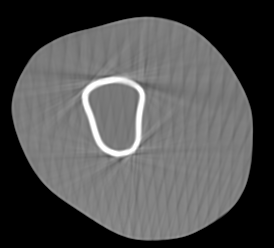

Involuntary subject motion is the main source of artifacts in weight-bearing cone-beam CT of the knee. To achieve image quality for clinical diagnosis, the motion needs to be compensated. We propose to use inertial measurement units (IMUs) attached to the leg for motion estimation. We perform a simulation study using real motion recorded with an optical tracking system. Three IMU-based correction approaches are evaluated, namely rigid motion correction, non-rigid 2D projection deformation and non-rigid 3D dynamic reconstruction. We present an initialization process based on the system geometry. With an IMU noise simulation, we investigate the applicability of the proposed methods in real applications. All proposed IMU-based approaches correct motion at least as good as a state-of-the-art marker-based approach. The structural similarity index and the root mean squared error between motion-free and motion corrected volumes are improved by 24-35% and 78-85%, respectively, compared with the uncorrected case. The noise analysis shows that the noise levels of commercially available IMUs need to be improved by a factor of $10^5$ which is currently only achieved by specialized hardware not robust enough for the application. The presented study confirms the feasibility of this novel approach and defines improvements necessary for a real application.